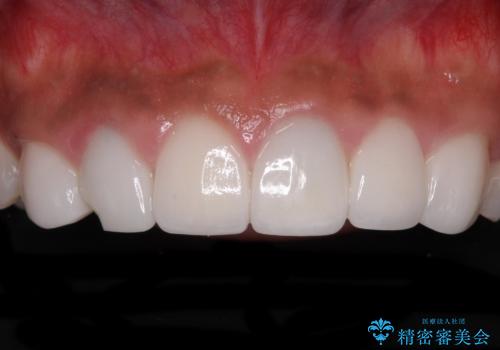

[前歯 セラミック治療] すぐに前歯が取れる きちんと治療して欲しい

![[前歯 セラミック治療] すぐに前歯が取れる きちんと治療して欲しいの症例 治療前](https://seimitsushinbi.jp/wp/wp-content/uploads/2021/01/9e6ce61e0bdd79ba9b3792484754c3e3-500x350.jpg?v=1609914925)